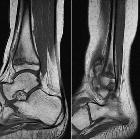

MRI

Useful for determining the extent of disease with whole-body STIR, including disease sites that may be clinically occult and can be used for subsequent follow-up. Findings can include:

- bone marrow edema

- periostitis

- soft tissue edema

- extension across the physis

- areas of post-gadolinium enhancement

Findings that should raise the possibility of haematogenous osteomyelitis over CRMO include:

- large fluid collection

- abscess

- fistulous tract

- bony sequestrum